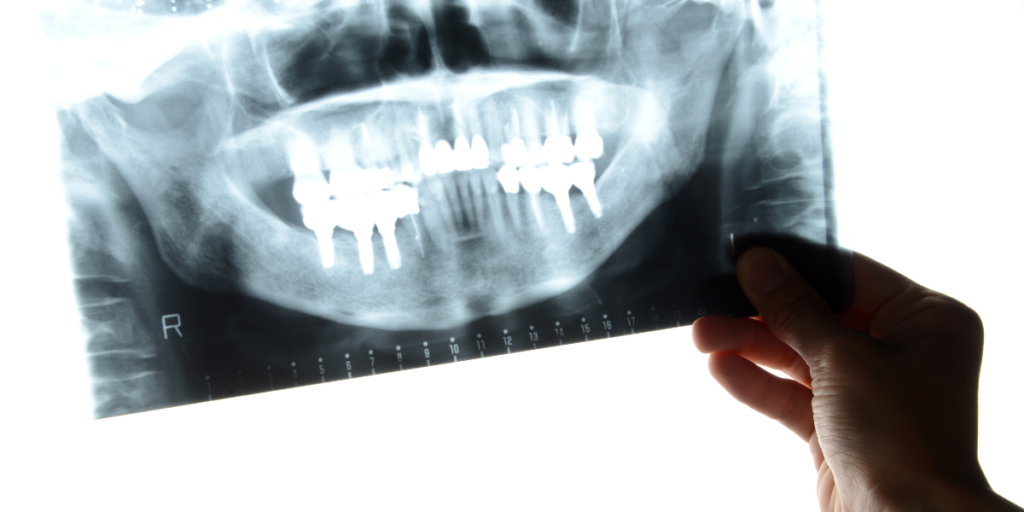

L’Esame RX Emimandibola, conosciuto anche come radiografia emimandibolare, è un esame radiologico che permette di ottenere immagini dettagliate della mandibola, dei denti e delle articolazioni temporo-mandibolari. Questa indagine è particolarmente utile per visualizzare in modo chiaro e preciso eventuali fratture ossee, dislocazioni, infezioni o cisti presenti nella mandibola.

Durante l’esame, il paziente viene posizionato davanti all’apparecchiatura radiologica. Un supporto apposito viene utilizzato per stabilizzare la mandibola, consentendo l’acquisizione di immagini chiare e precise. I raggi X emessi attraversano i tessuti molli del viso e vengono assorbiti dalle strutture ossee, generando immagini che vengono successivamente analizzate dal radiologo o dallo specialista in odontoiatria del Poliambulatorio S-Medical Group di Sora.

• Fratture mandibolari: causate da traumi o incidenti, visibili come discontinuità nell’osso.

• Ascessi e infezioni dentali: evidenziati come zone scure intorno alla radice dei denti.

• Cisti e tumori mandibolari: rilevati come aree di densità anomala all’interno della struttura ossea.